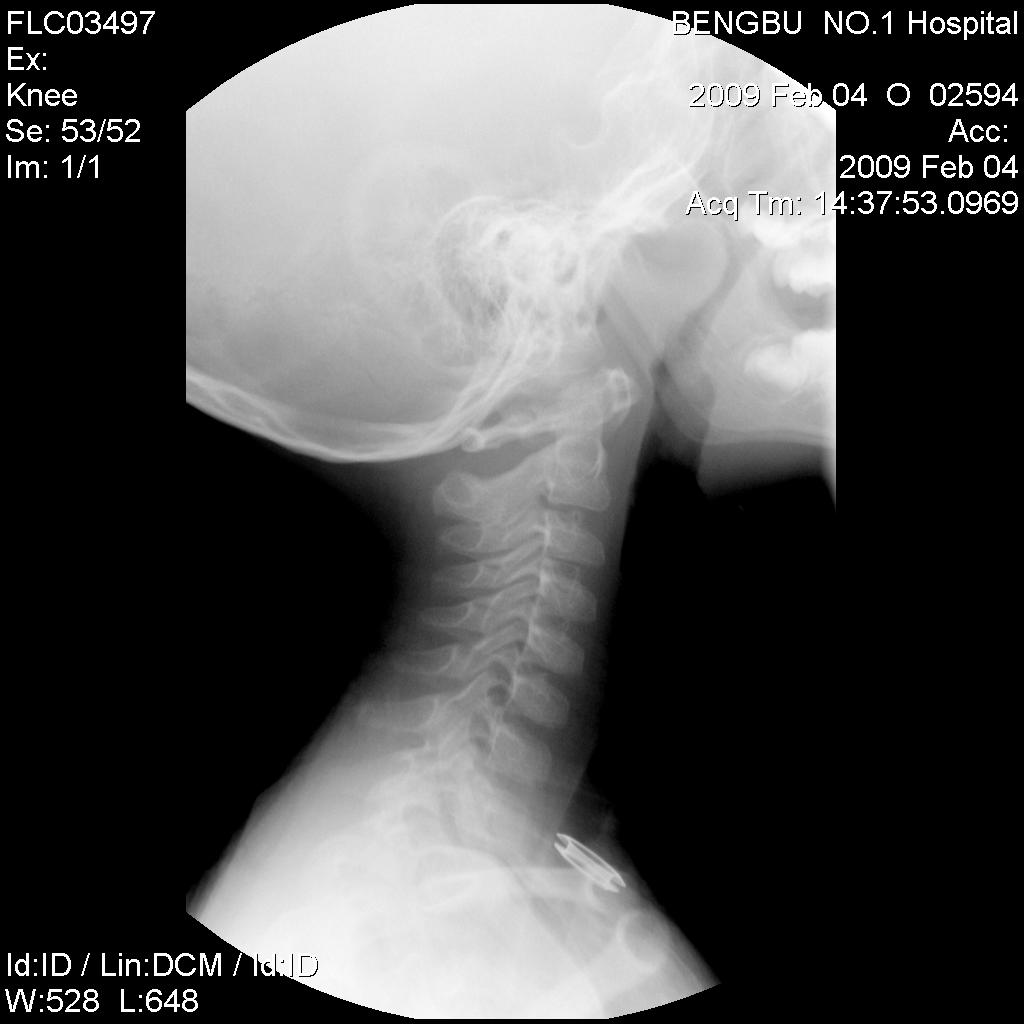

标题: PED1736:男,6岁,打鼾1年。 [打印本页]

标题: PED1736:男,6岁,打鼾1年。

腺样体肥大,胸锁关节上方金属异物是衣服上的吗?

鼻咽腺样体肥大。

胸锁关节上方金属异物是衣服上的.

支持腺样体肥大。不是一般的大。

咽后软组织影向前挤压气道,考虑腺样体肥大.